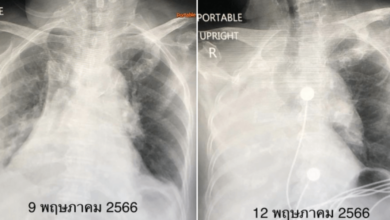

หมอมนูญ เผย พบผู้ป่วยโควิด XBB ปอดแฟบ 2 ราย เตือนเสี่ยงเสียชีวิต

หมอมนูญ เผย พบผู้ป่วยโควิด XBB ปอดแฟบ 2 ราย เตือนผู้ติดเชื้อที่มีโรคประจำตัวเยอะและอายุมาก มีโอกาสป่วยหนักและเสียชีวิต นพ.มนูญ ลีเชวงวงศ์ แพทย์เฉพาะทางด้านโรคระบบการหายใจ โพสต์ข้อความเฟซบุ๊กเปิดเผยว่า